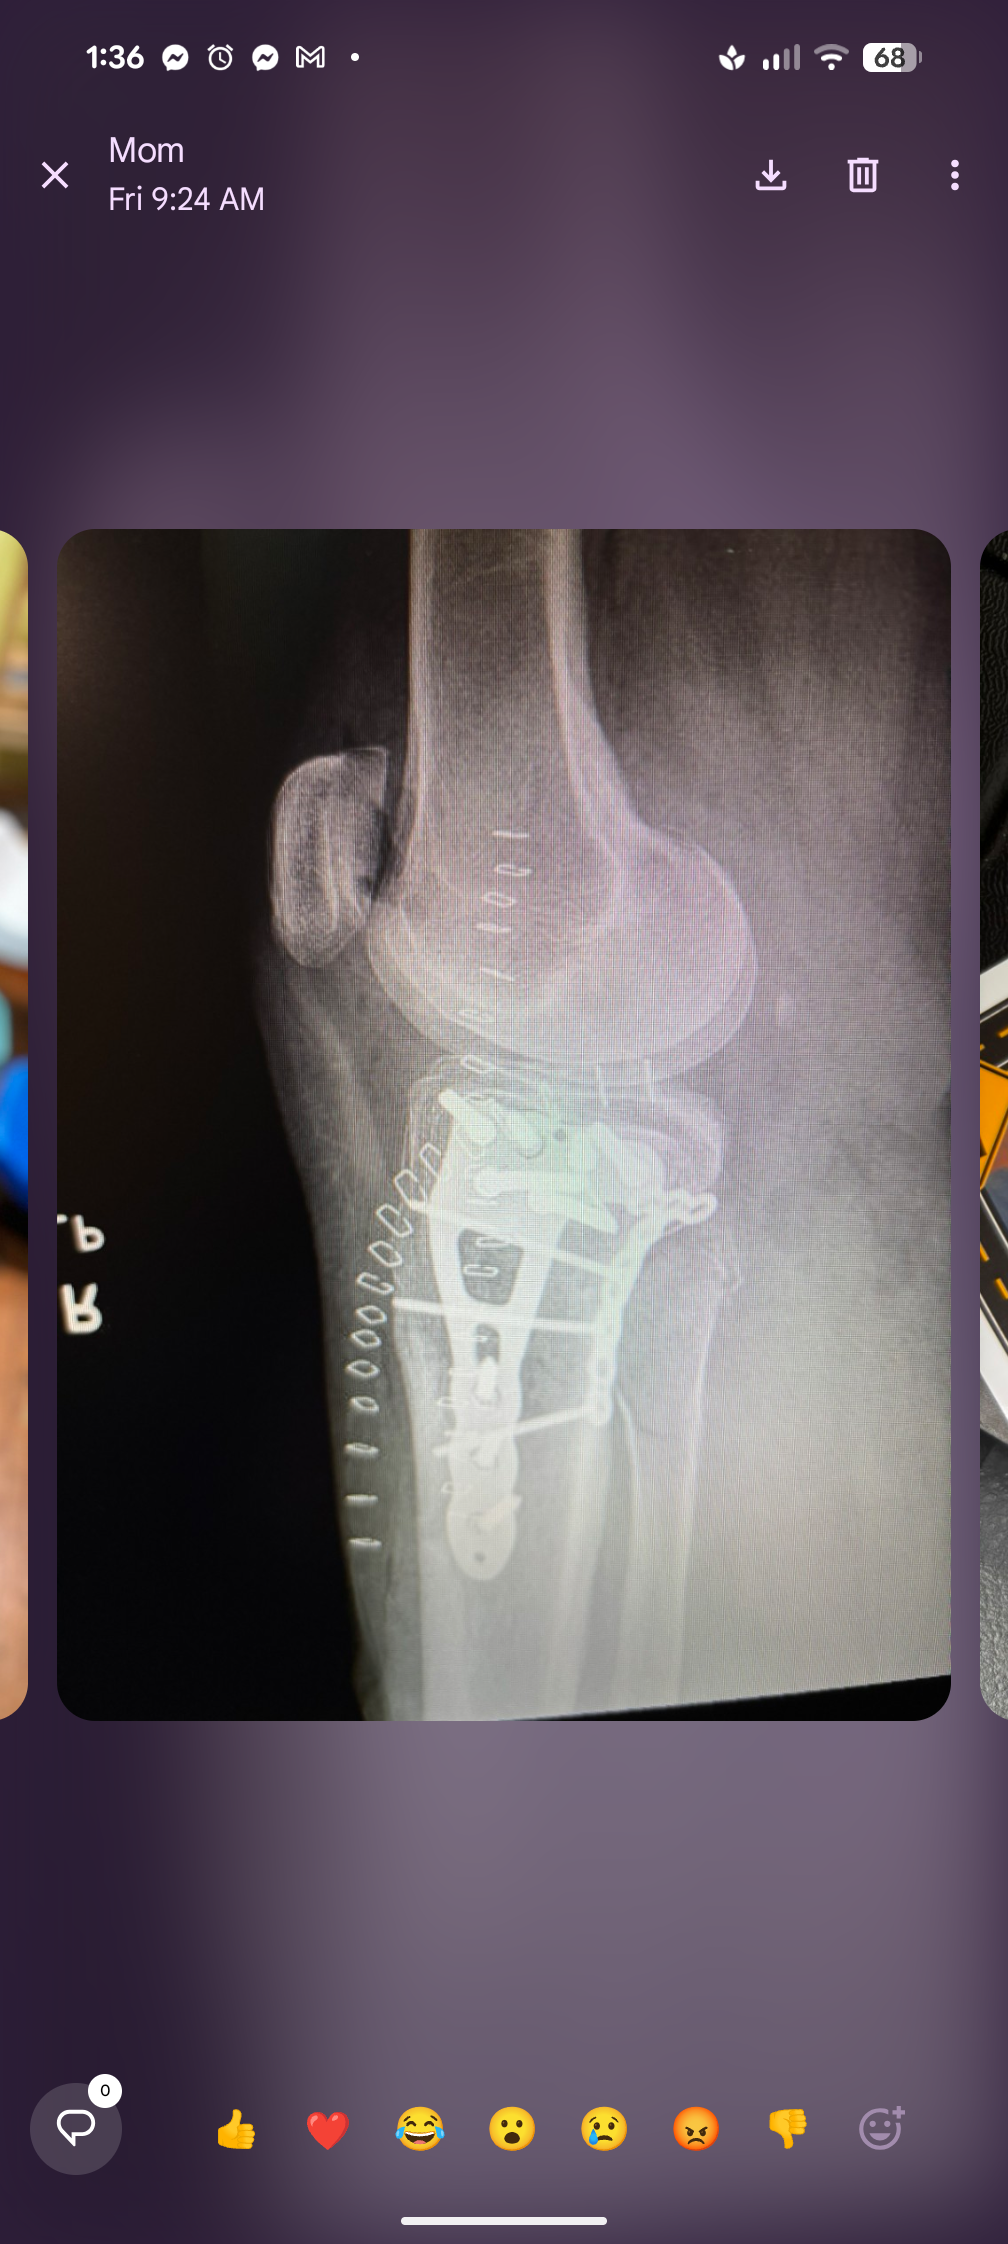

On New Year's Eve, my mom suffered a serious accident when she fell off a ladder and broke her leg. She underwent surgery on New Year's Day to repair the break, and now faces a long road to recovery. For the next three months, she is bedridden and unable to put any weight on her leg, with another surgery already planned and a total recovery time that could stretch to a year or more. She requires round the clock care for repositioning, toileting, and pain management. As her primary caregiver, I have had to put off working so I can be home to take care of her full-time. This has put us in a difficult financial position, as we are now falling behind each month while I am not working. I had a full time career lined up that we were going to transition to prior to the accident. However, now we're behind on overhead each month plus other expenses related to caring for my mom.